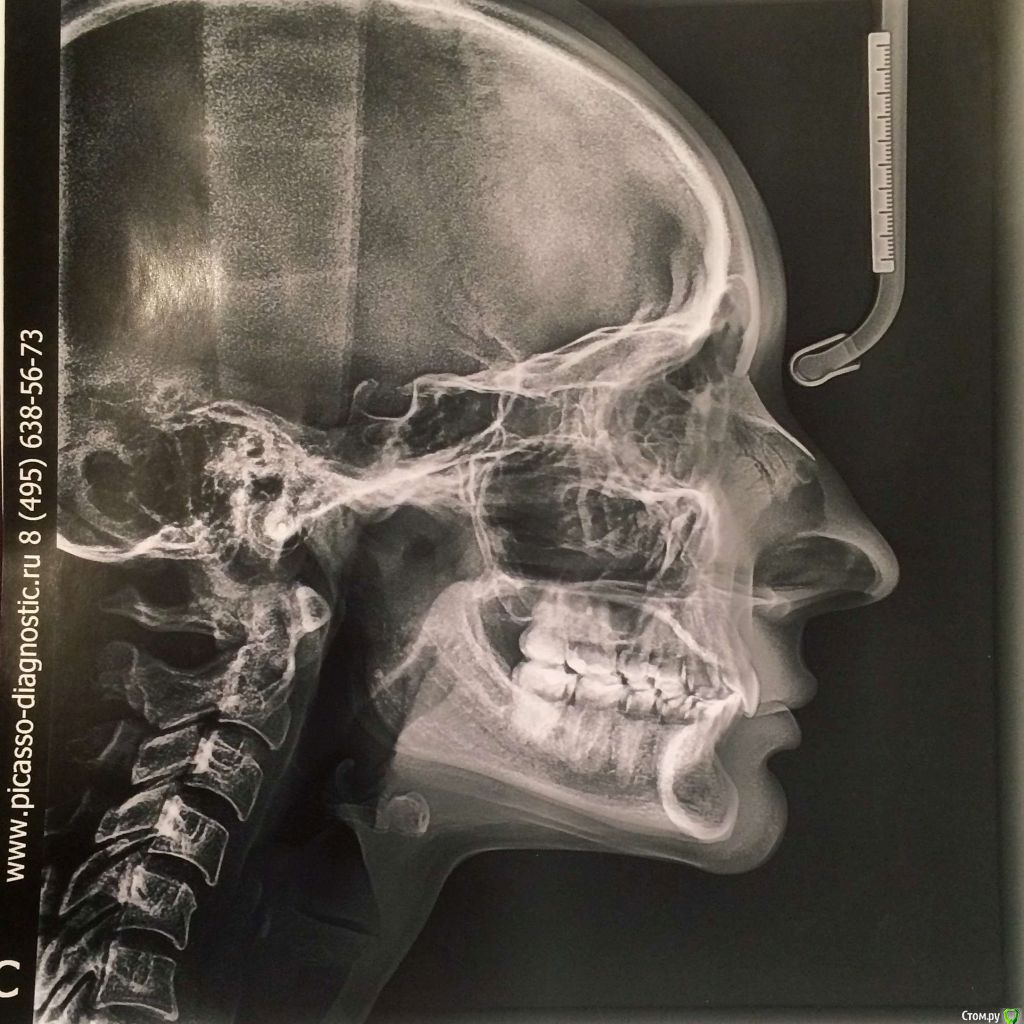

Добрый день! Очень прошу помочь с выбором врача или рекомендаций по лечению. С 2010 по 2012 год я носила брекеты (зубы были ровные, но с левой стороны верхня челюсть полностью перекрывала нижние, не было контактов, происходило стачивание). Затем с 2012 по 2016 год мне пытались исправить зубы нижней челюсти, я носила разные каппы, пластинки, то есть зубы все это время не фиксировали в определенном положении. Затем наконец в 2016-2017 году я относила полгода корректирующую каппу, которая более-менее выровняла мне нижний ряд (там была скученность). Все это время пломбы на жевательных зубах мне не меняли, они очень сильно сточились, и мне рекомендовали их заменить. Но как раз в это время у меня заболел сустав с правой стороны (на фото он соответственно слева, где и наблюдается ассиметрия). Я стала ходить по ортодонтам-ортопедам, одни говорили, что у меня все супер с прикусом, другие говорили, что клыки не под тем углом и надо снова ставить брекеты. Устав от хождений, я обратилась за диагностикой в небезызвестный центр междисдисплинарной стоматологии. Сделала там полную диагностику, по результатам которой мне предложили либо исправить брекетами клыки и поднять прикус керамическими вкладками, либо без брекетов, но тогда ставить на клыки также вкладки. Эта процедура проводится аж в три этапа и стоит как крыло самолета. Я прилагаю результаты моей диагностики. Обратилась за консультацией к другому ортопеду, который заверил, что можно обойтись временными и затем керамическими вкладками. Но помимо прикуса меня волнует ассиметрия улыбки, которая появилась в последнее время. Во-первых, я вижу невооруженным глазом, что зубы с правой стороны по высоте короче, чем с левой, то есть они меньше закрывают нижние зубы, чем с противоположной стороны, это же видно и на фото. Во-вторых, справа уголок губы при улыбке опускается как бы к низу, в отличе от левой стороны, где он идет ровно. В-третьих, с этой же правой стороны при улыбке мыщца начинается дергаться... Сейчас я уже запуталась, к какому врачу мне обращаться с данной проблемой: к ортодонту, к ортопеду, либо это гипертонус мыщц (хотя в закрытом состоянии эта ассиметрия не так заметна) Заранее благодарю за рекомендации.

Вам необходим врач-ортокраниодонт. Пытаться найти решение проблемы только на уровне зубов будет крайне трудно, да и бесполезно. Это сравнимо с симптоматическим лечением, когда идёт борьба только с симптомами заболевания, но никак не влияя на главную причину. Природа Ваших проблем (ДВНЧС, асимметрия) кроется в черепе, а точнее, в имеющимся его искажении